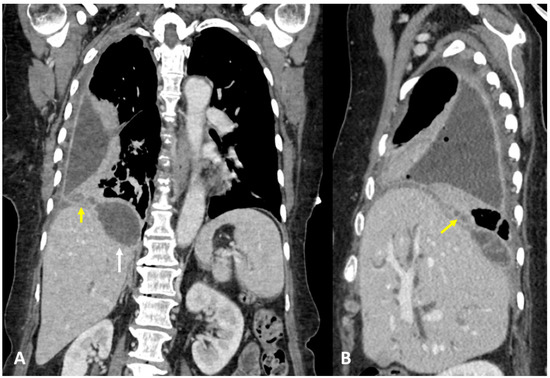

3.1. Case #1: Hepato-Thoracic Fistula

3.2. Case #2: Hepato-Thoracic Fistula

3.3. Case #3: Hepato-Thoracic Fistula